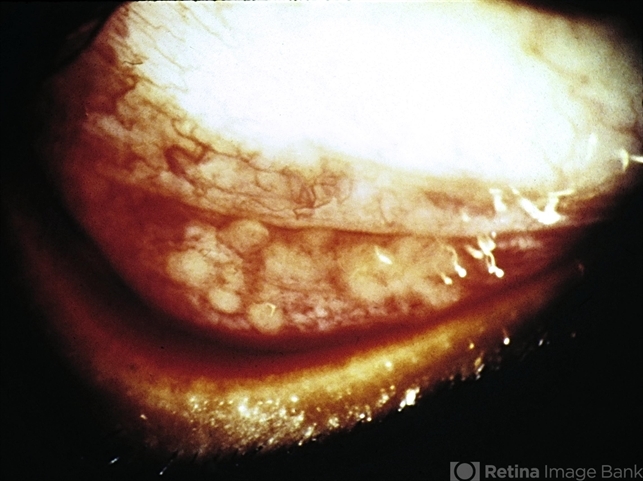

- granuloma, sarcoidosis

- Conjunctival granulomas in a case of sarcoidosis.